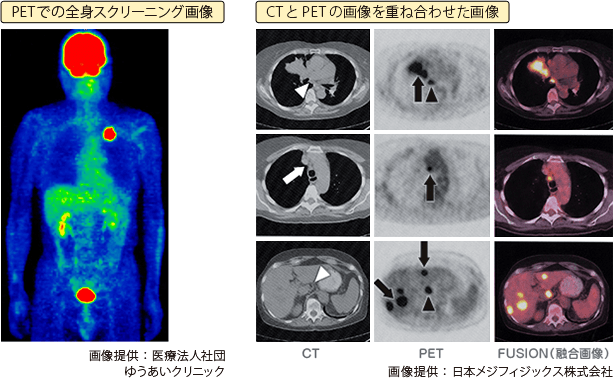

肺がんの検査でPETが行われるのは、肺がんの確定診断後および治療中や治療終了後に転移の有無や部位を調べるときです。

肺がんのPET検査で広く使用されている放射性医薬品(ガンマ線という放射線を放出するアイソトープを用いた注入剤)は18F-FDG(18F-フルオロ・デオキシ・グルコース)というものです。このため、18F-FDGを使用するPET検査のことをFDG-PETと呼ぶことがあります。

がん組織の多くはブドウ糖代謝が活発なため、FDGはがん組織に集まります。そこから発生するガンマ線をとらえることによって、がんの有無やおおよその位置がわかります。

PET検査では、18F-FDGを注射して1時間ほど安静にした後、PET装置でガンマ線を検出します。

最近は空間分解能を補う目的で、X線CT(通常のCTです)とほぼ同時に画像を撮ることのできるPET-CTが広まりつつあります。PET検査が、「ブドウ糖の取り込み」というがん細胞の働きを画像化するのに対し、CT検査はX線を使って腫瘍の位置や大きさを画像化します。これら2つの画像を重ね合わせること(フュージョン)で、腫瘍の性質(良性か、悪性か)や位置についての詳しい情報が得られます。PET-CT検査の流れはPETだけの場合とほぼ同じで、費用の目安はおよそ10〜12万円くらいです(保険適用の場合はこの1〜3割負担)。

PET検査の弱点は、他のアイソトープ検査と全く同じで、グルコースが「がん細胞だけに集まるわけではない」ことです。がん以外のグルコース代謝の活発な組織、炎症部位や正常な脳にもFDGは高濃度に集積します。このため、本当はがんであるのに正常または良性と判断してしまう偽陰性や、正常または良性なのにがんと判断してしまう偽陽性という間違いが起こることがあります。

サンプルの写真をご覧ください。頭部に強い集積がみられます。これは脳組織にFDGが高濃度に集まった結果であり脳転移を示しているのではありません。